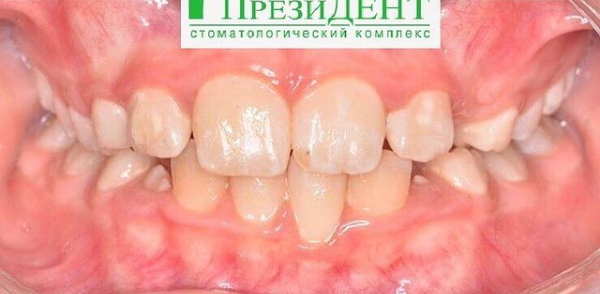

Врач Заводова (Рыбась) Анна Викторовна принимает в стоматологическом комплексе ПРЕЗИДЕНТ НА ЛЮБЛИНСКОЙ в Москве. Имеет рабочий стаж 21 год. Специализируется на ортодонтии, по которой клиника оказывает 3 услуги. Имеет 4 работы до/после в портфолио. Квалификация специалиста подтверждена 15 лицензиями, сертификатами и наградами. Для уточнения дополнительной информации о специалисте или записи на прием можно позвонить по телефону

Установка брекетов

Установка брекетов в Москве

от 200 000 ₽